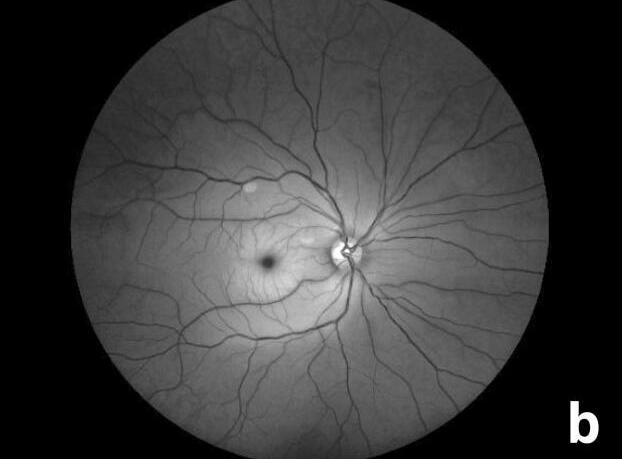

La evaluación del segmento anterior se encontró dentro de normalidad, sin rubeosis iridis y la presión intraocular fue de 18 mmhg ambos ojos (AO). Posterior a la dilatación pupilar, en la fundoscopia y en fotos del polo posterior, presentaba blanqueamiento retiniano con mancha en rojo cereza en OD [figura 1a,b] . Dentro de la evaluación complementaria, se realizó una tomografía de coherencia óptica (OCT) macular, con

(a) Papila de bordes definidos excavación 0.3 emergencia central de vasos, ISN Tconservado, relación va 3-2, estrechez arteriolar, placa de hollenhorst en arcada vascularsuperior, palidez retinal en los 3 mm centrales de la retina, se evidencia mancha rojo cereza.

(b) Foto aneritra que resalta la vascularización retinal.

hallazgos de hiperreflectividad y engrosamiento de capas internas de la retina, las capas externas estaban intactas en OD; hallazgos sugestivos de oclusión de arteria central de la retina (OACR). (Imagen 1 ).

Se observa una imagen de OCT de ojo derecho que evidencia interfaz vitreomacular sin alteraciones, evidencia de hiperreflectividad de capas internas de la retina y banda hiperreflectiva a nivel de las capas externas, grosor central aumentado.